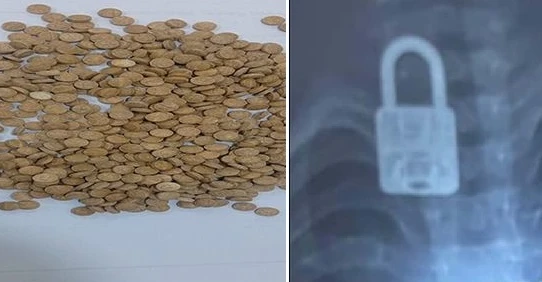

حبوب المخدرات المضبوطة والقفل داخل جسم الطفل بفحص الأشعة

حبوب المخدرات المضبوطة والقفل داخل جسم الطفل بفحص الأشعة

وعن تفاصيل ضبط المخدرات في الرمادي، أوضحت شرطة الأنبار في بيان ورد لوكالة شفق نيوز، أن قوة أمنية داهمت بعد استحصال الموافقات القضائية دار المتهم (أ.د.ع.م) وتم إلقاء القبض عليه.

وأشارت إلى أن عملية تفتيش الدار أسفرت عن ضبط 615 حبة مخدرة من نوع كبتاغون، مبينة أنه تم تنظيم محضر ضبط أصولي وتسليم المتهم مع المضبوطات إلى الجهات المختصة لاتخاذ الإجراءات القانونية بحقه.

وبعد إجراء فحص بالأشعة السينية للطفل تبين وجود "قفل" داخل جسمه، وعلى إثر ذلك، بحسب دائرة الصحة، تم التنسيق مع مدينة الصدر الطبية / قسم جراحة القلب والأوعية الدموية لاستخراج "القفل"، وتم ذلك بنجاح عن طريق الناظور، والطفل الآن بحالة صحية جيدة.